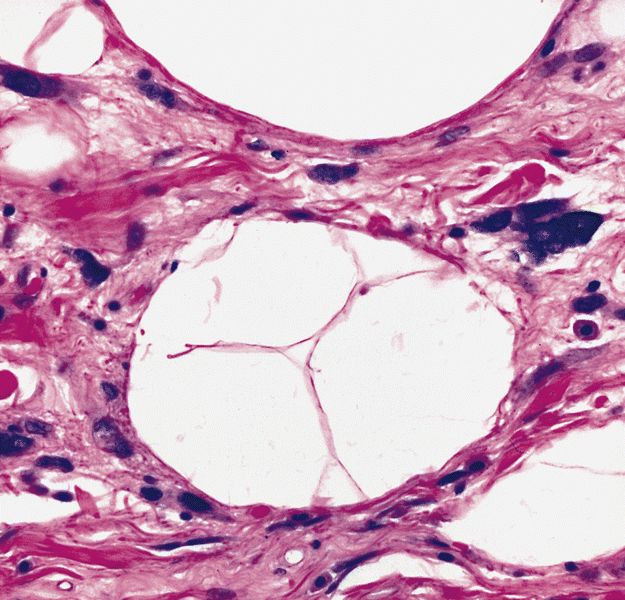

Microscopic (histologic) images

Contributed by Michael Clay, M.D., Melanie Bourgeau, M.D. and AFIP

Metaplastic change:

Microscopic (histologic) description

- Depends on subtype, generally composed of mature fat with variably sized adipocytes and bands of fibrotic stroma containing spindle cells with enlarged, hyperchromatic nuclei

- Can be markedly atypical

- Atypical cells are more commonly found in fibrous septa and in a perivascular distribution

- Lipoma-like subtype

- Most common subtype

- Scattered atypical cells may be diffuse or exceedingly rare

- Frequently contains lipoblasts

- Nuclei with sharply outlined vacuoles (Lochkern cells) are enlarged and can appear hyperchromatic but are normal adipocytes cut in cross section

- These do not qualify for the diagnosis; the same goes for atrophic skeletal muscle fibers, which can simulate atypia on an otherwise typical lipoma

- Histiocytes in areas of fat necrosis can simulate atypical cells

- Lipoblasts are neither necessary nor sufficient for diagnosis

- When present they are generally multivacuolated versus the signet ring lipoblasts commonly seen in myxoid liposarcoma